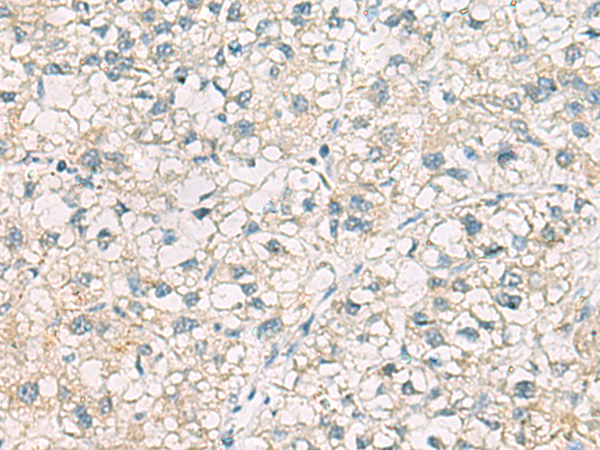

分类: 科研抗体货号: P02407别名: hSAD1应用: IHC反应种属: Human, Mouse, Rat